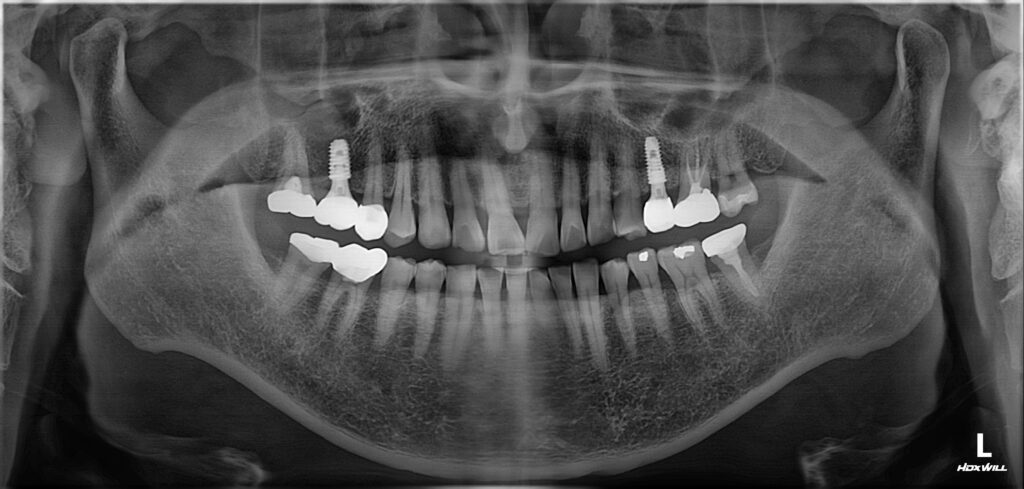

무절개 임플란트의 가장 큰 장점은

출혈과 부종이 적다는 것으로 잇몸을 열지 않으므로

봉합 과정이 생략될 수 있으며,

이는 곧 통증의 감소와 빠른 일상 복귀로

이어지게 될 수 있습니다.

임플란트는 자연 치아와 달리 신경이 없어

이상이 발생해도 통증으로 바로 인지하기

어려운 경우가 있는데요.

따라서 시술 이후 정기적인 검진과 스케일링,

교합 점검 등 임플란트 관리가 중요합니다.

관리가 제대로 이루어지지 않을 경우

주위염이 발생할 수 있으며

이는 유지 기간에도 영향을 줄 수 있습니다.